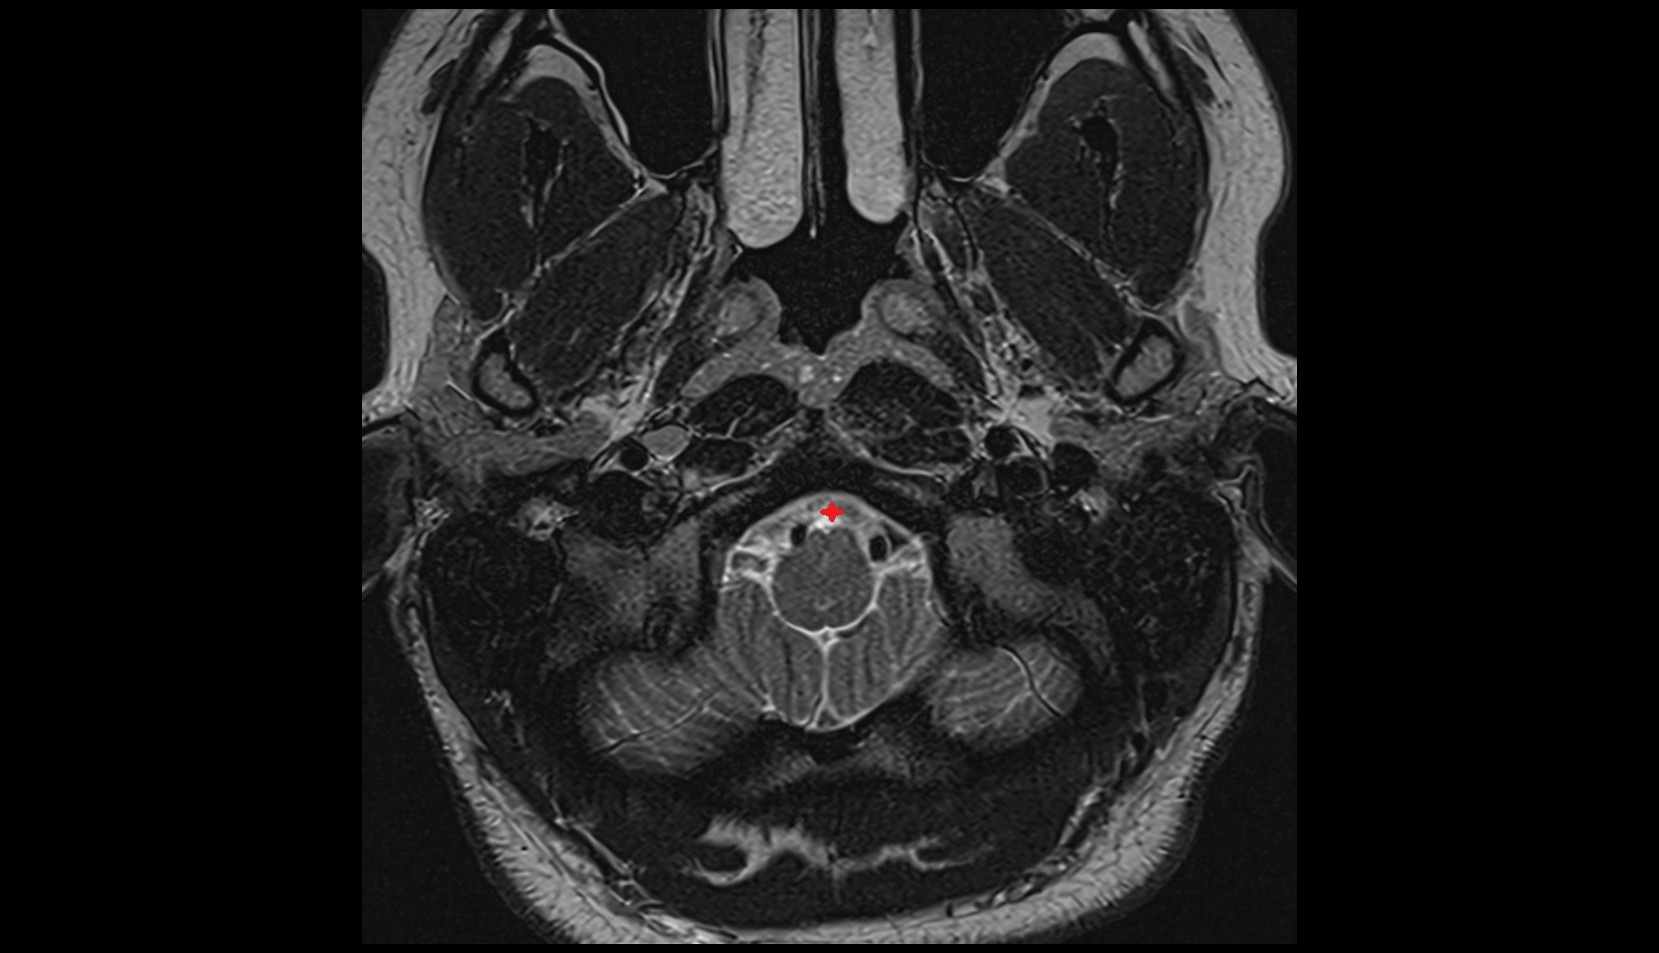

- Upper cervical spinal cord

- Spinal cord